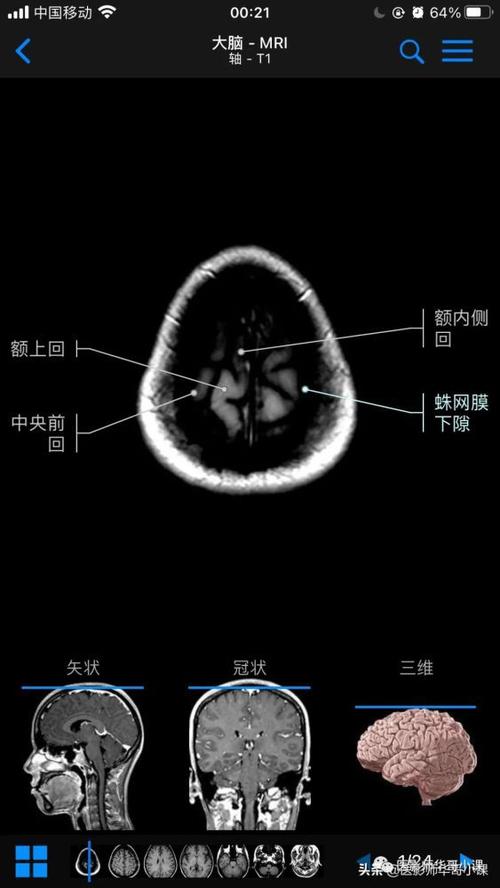

脑部主要结构mri横断位解剖

高清mri图颅脑磁共振mri解剖